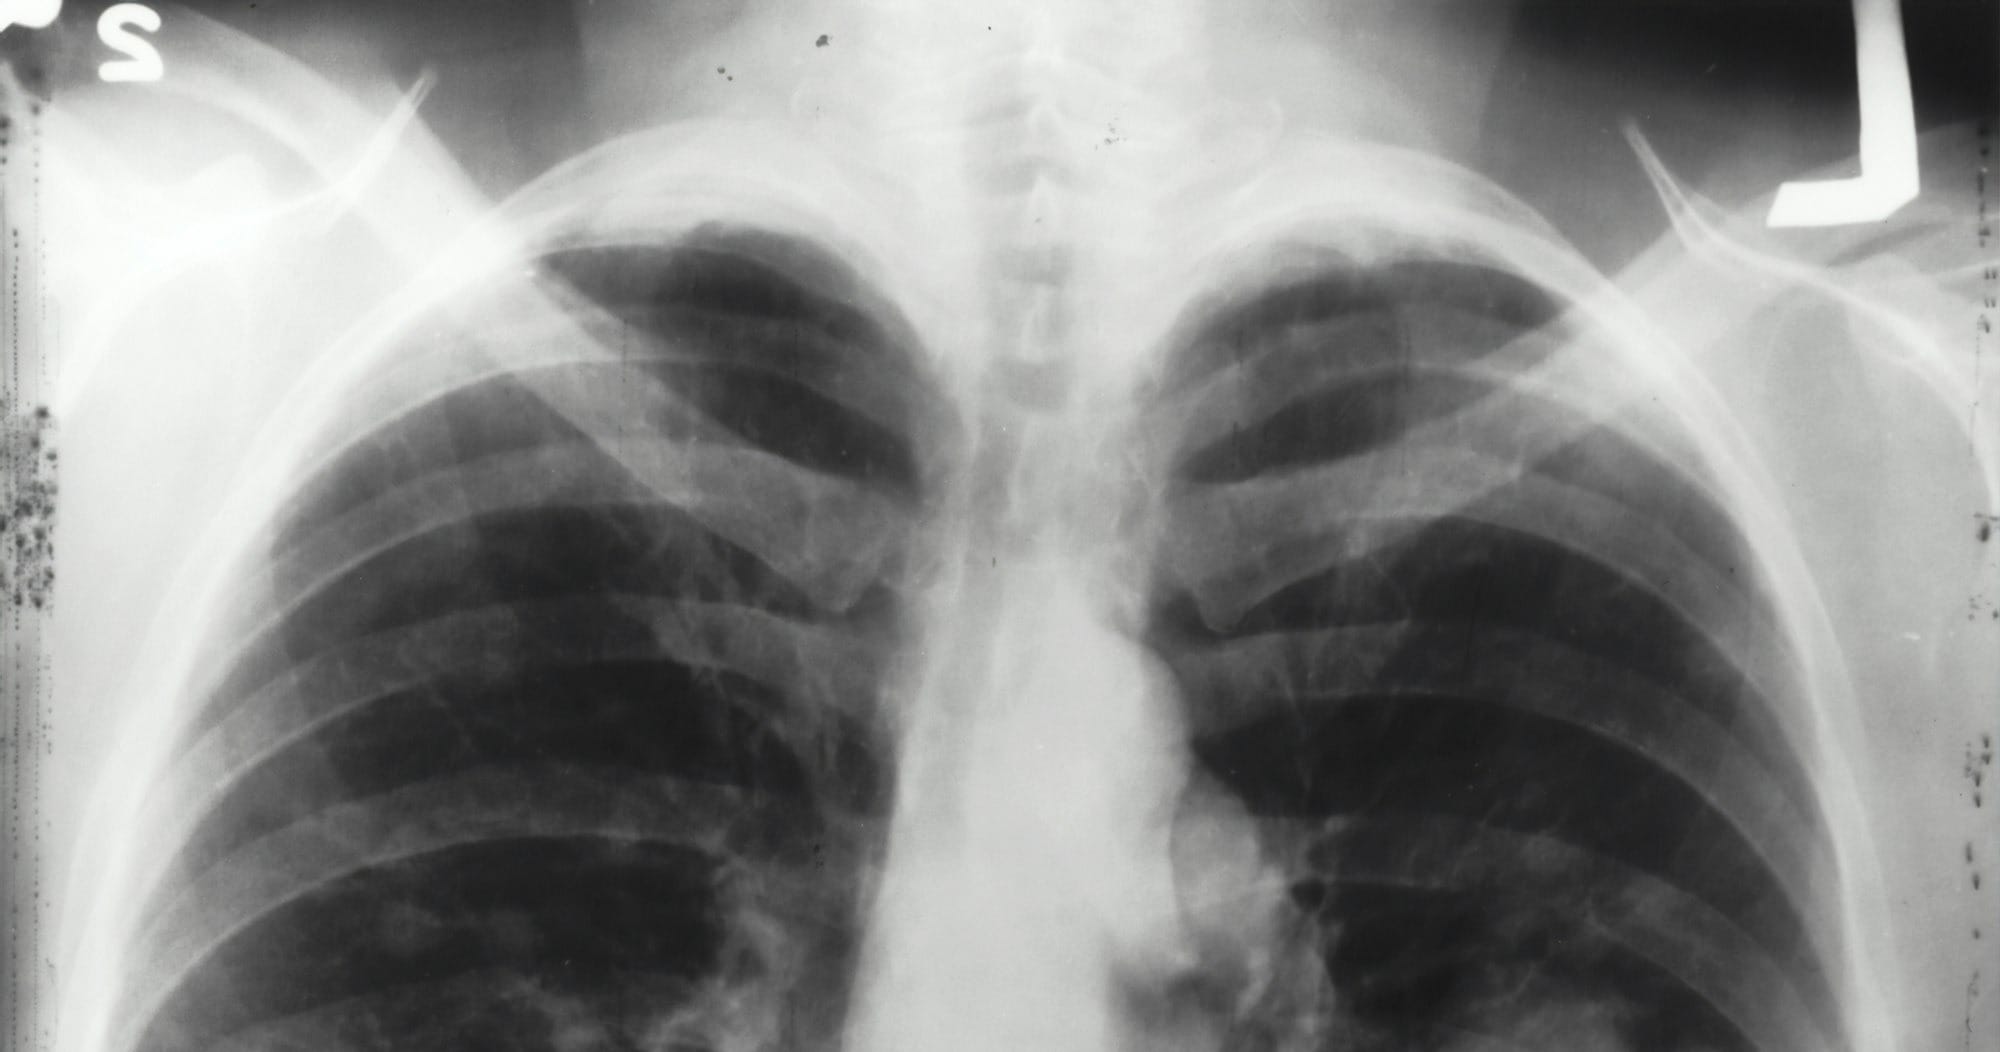

Pneumonia is a significant health concern, particularly for the elderly, young children, and individuals with weakened immune systems. It is a respiratory infection that inflames the air sacs in one or both lungs, which may fill with fluid. To combat the risks associated with pneumonia, vaccines like the pneumococcal conjugate vaccine (PCV) and the pneumococcal polysaccharide vaccine (PPSV23) are essential tools in preventive healthcare.